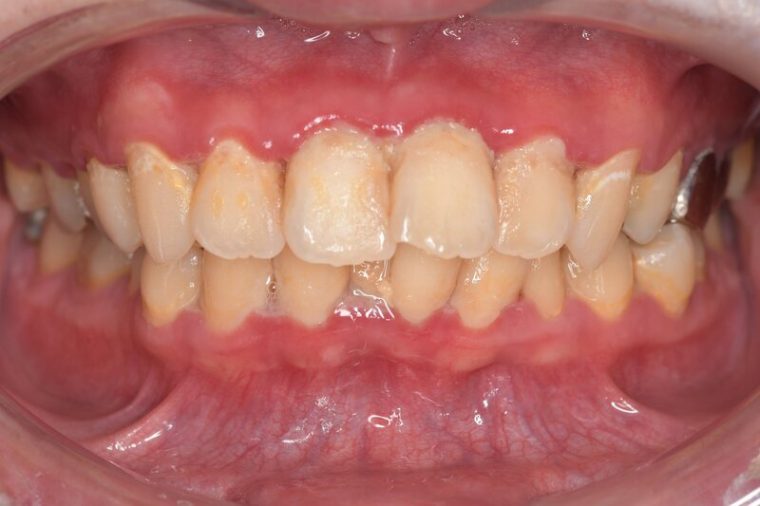

CASE 11

Before

After

| 年齢・性別 | 32歳・男性 |

|---|---|

| 主訴 | 歯石をとりたい |

| 治療内容 | スケーリング |

| 治療期間 | 30分 |

| 治療費 | 1,500円(保険診療) |

| リスク・副作用 | 知覚過敏、歯肉退縮、出血 |

| 治療方針 | 今後も定期的にクリーニングを行っていきます。 |